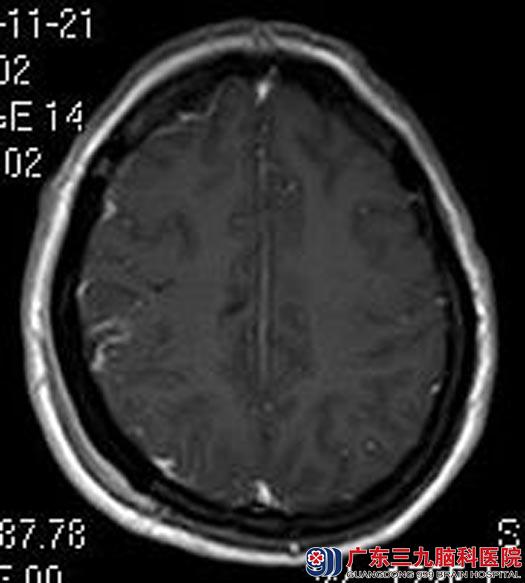

两年多的头晕,一直以为是颈椎病,竟然发现是脑肿瘤,家人立即带着她来到广东三九脑科医院。头颅MR检查提示右侧额顶部大脑凸面占位性病变,大小约46mm×55mm×49mm,考虑脑膜瘤可能性大。

确诊后,王女士要求手术切除治疗。由综合神经外科鲁明主任主刀在全麻下行右额顶脑膜瘤切除术,术中导航定位肿瘤体表面积,显微镜下见肿瘤呈灰白色,质韧、血供一般,边界清,镜下顺利全切肿瘤。术后王女士未出现语言、肢体等功能障碍。术后病理结果:纤维型脑膜瘤(WHO I级)。